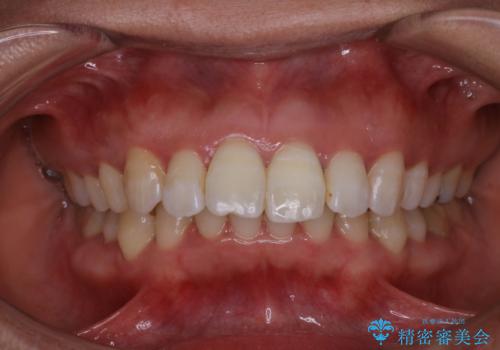

- 前歯の色が気になるとのことでご相談にいらした患者様です。診断の結果、前歯は2本とも失活していたために精密根管治療から治療を開始しました。根管治療後にウォーキングブリーチを行うことで歯の色をトーンアップさせました。患者様より周囲の歯も全体的に白くしたいとのご希望があったため、オフィスホワイトニングも併せて行いました。

- 4万円(精密根管治療・オフィスホワイトニングは除く)費用は治療当時の料金となります